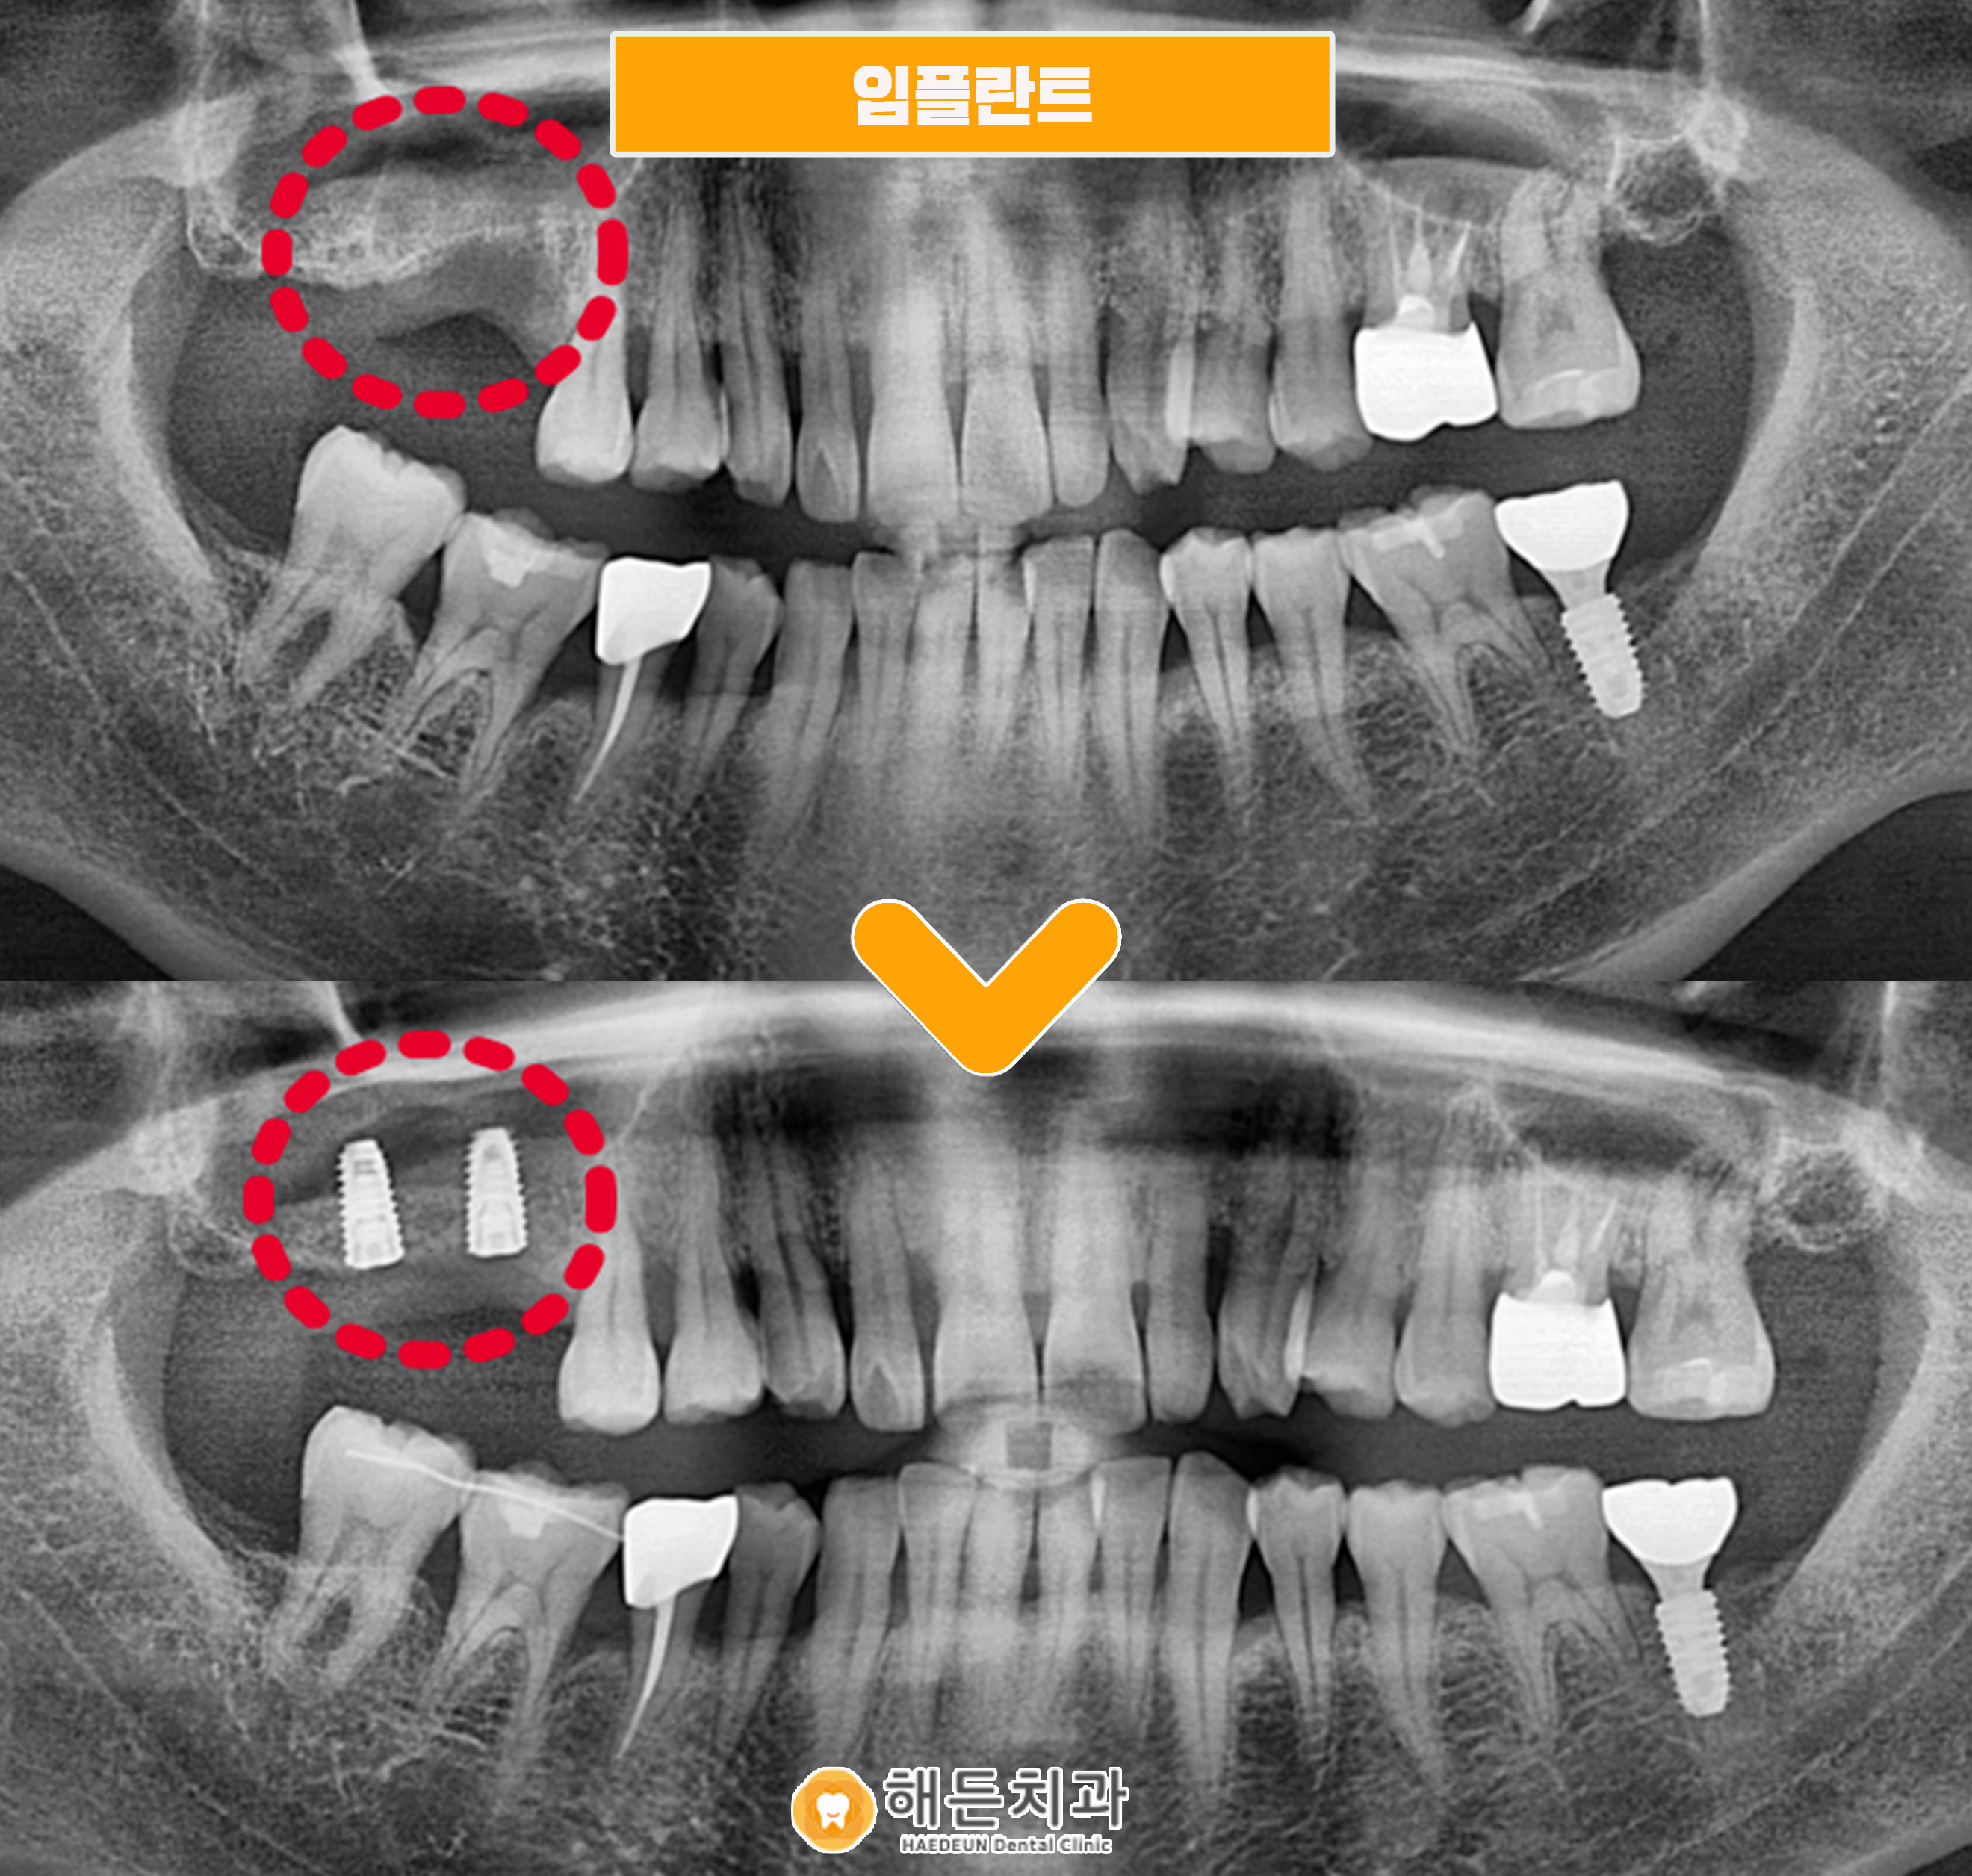

상악동 거상술을 통해 부족한 뼈를 보강하여 임플란트를 안정적으로 식립하였고, 임플란트 식립 후에 픽스처 주변으로 잇몸뼈가 부족한 부분에도 인공뼈를 이식해 드렸습니다.

.

인공뼈와 픽스쳐가 단단하게 유착될 때까지 충분히 기다린 후, 골 결합 정도를 수치로 확인할 수 있는 장비인 Osstell을 통해 식립이 안정적으로 잘 되었는지 확인한 뒤 최종 보철물까지 마무리 해드리기로 하였습니다!

🦷 전 >후 🦷

치료기간 : 2021. 07 ~ 2021.11